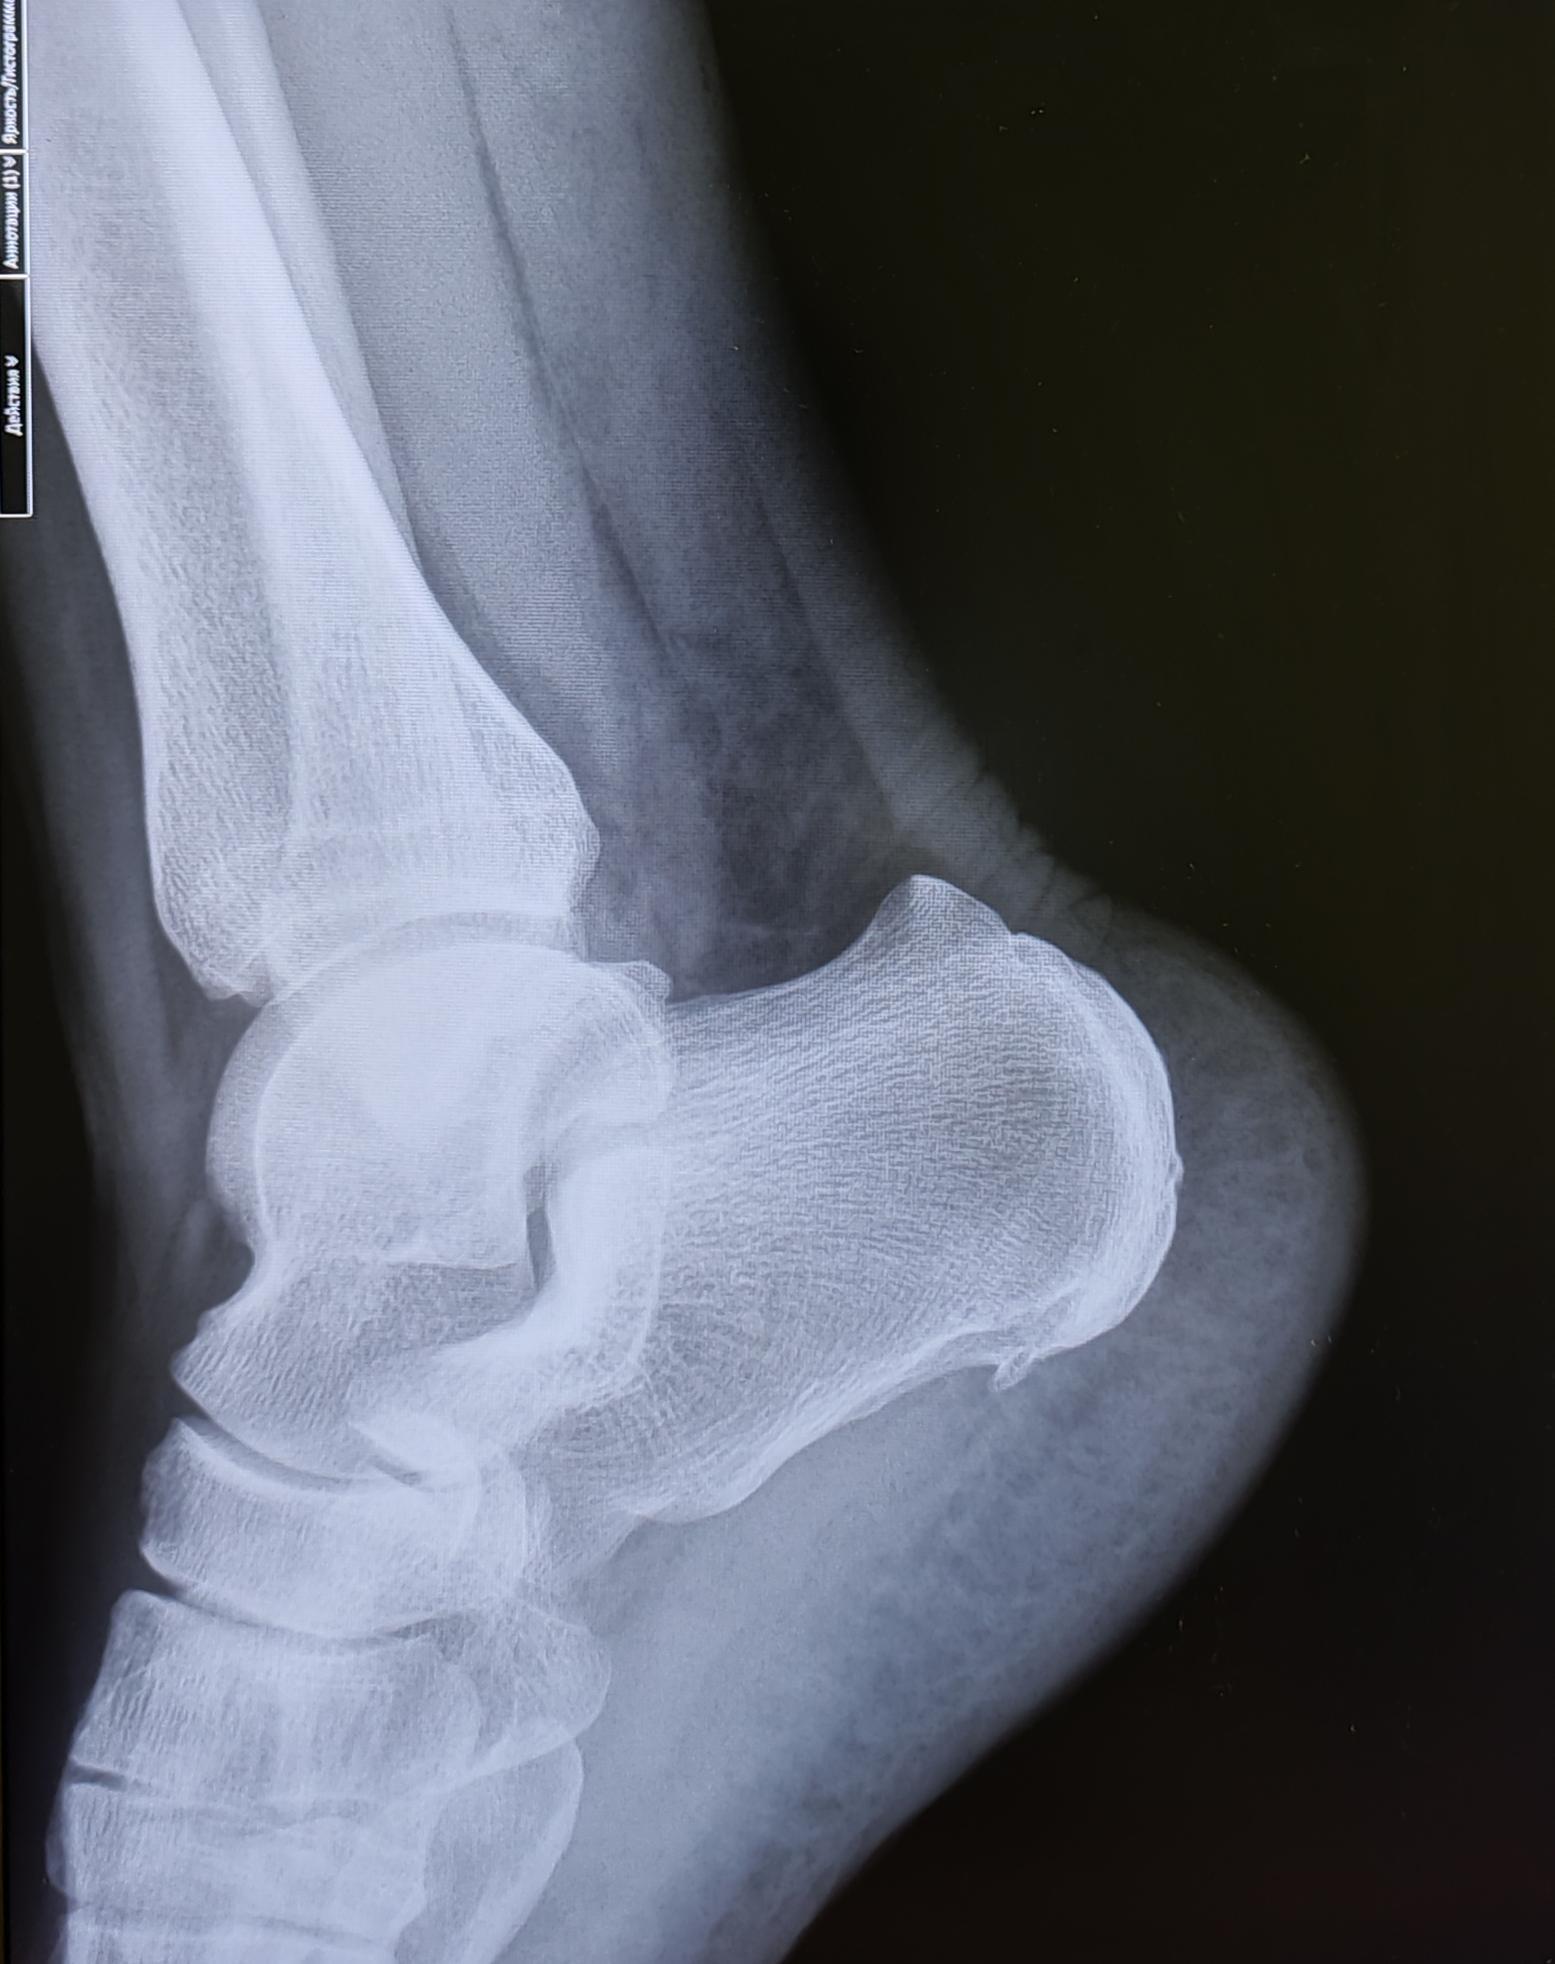

Описание: на Р-граммах правой и левой пяточных костей-травматических, деструктивных изменений не выявлено, структура костной ткани не изменена. В месте прикрепления подошвенных апоневрозов к буграм пяточных костей-визуализируются костные экзостозы. Верхняя часть бугров пяточных костей увеличена в размерах, имеет треугольную форму на широком основании. Заключение: Двусторонняя деформация Хаглунда. Двусторонние пяточные "шпоры".

При отсутствии длительного анамнеза воспалительного процесса, частых обращений с болевым синдромом, стац. лечения по поводу болевого синдрома, решение выносится на основании ст.65(Хирургические болезни и поражения костей, крупных суставов, хрящей:) г, Б-3:призывник годен к военной службе с незначительными ограничениями.